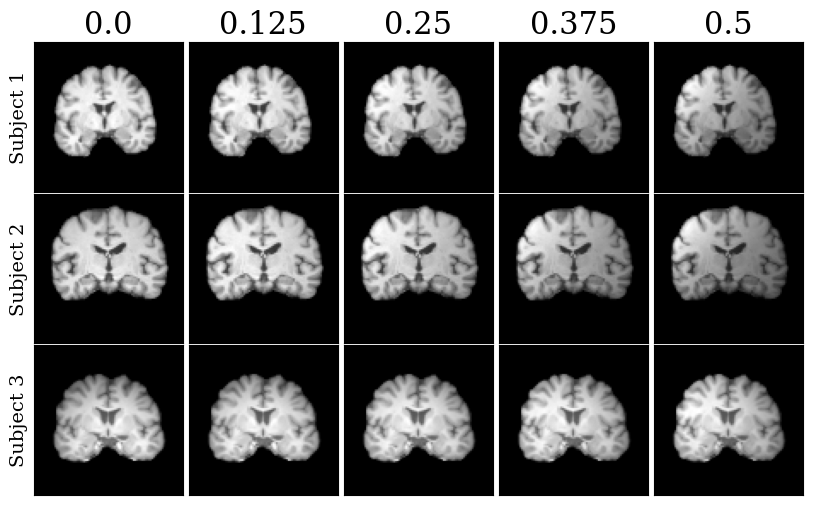

Refer to caption

Fig. 4: Representative registration results on different volumes from a pair of subjects, for unsupervised KM variants. Registered images are performed for different TPS λ𝜆\lambda’s and affine transformations. Deformed grids are depicted.